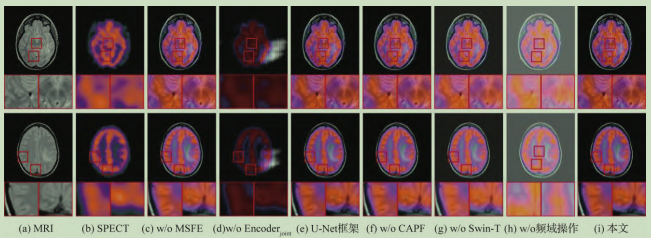

渐进特征提取和频域信息补充的多模态医学图像融合